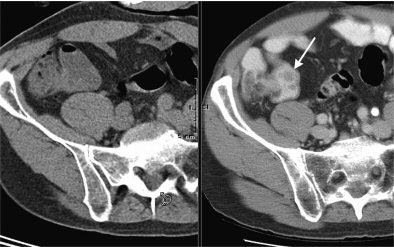

![]() |

| The image shows a patient with lymphoma and nodules in terminal ileum (arrow). The nodules are not apparent on PET/CT without benefit of oral contrast. The finding is clinically significant, because it could represent extranodal spread of lymphoma. It proved to be Crohn's disease after colonoscopy and surgical removal. "Limitations of CT during PET/CT" (Journal of Nuclear Medicine, Vol. 48:10, pp. 1583-1591). Reprinted by permission of SNM. |